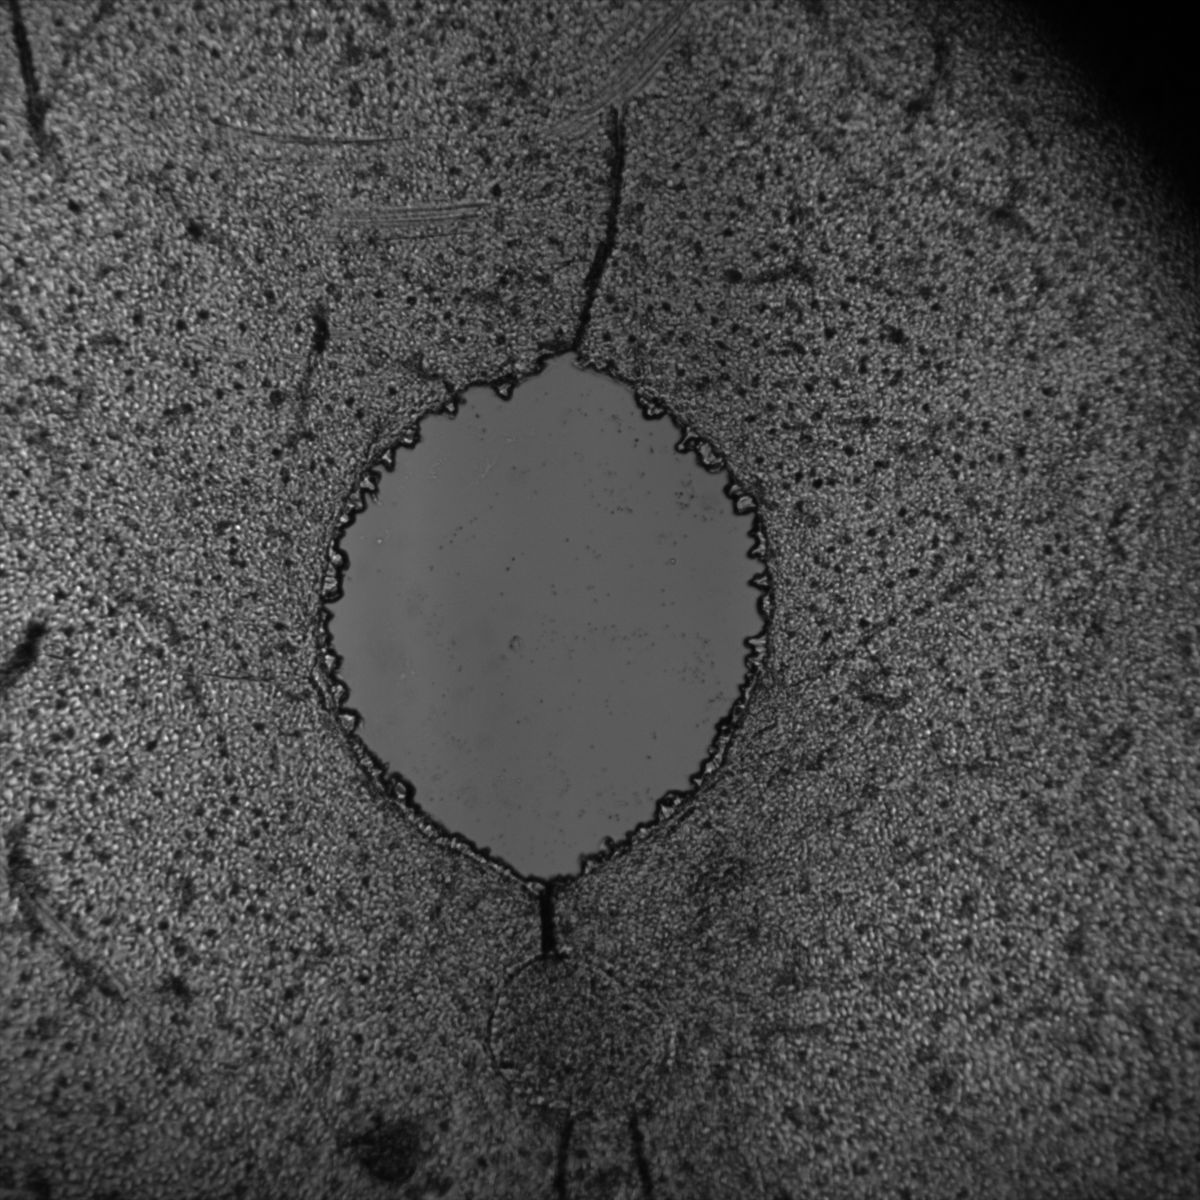

Healthy Eye

Overview 1

Overview 2

Overview 4

Blast Eye